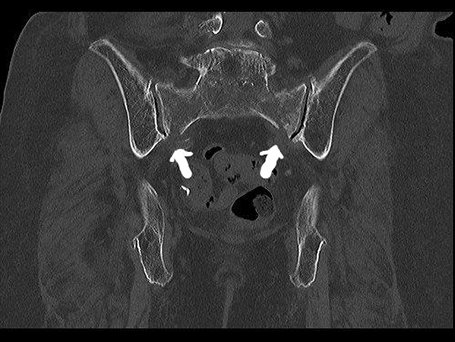

Hintere beiderseitige Kreuzbeinfraktur

Patientin mit beiderseitigem Bruch des Kreuzbeins und Querfraktur (U-Shaped fracture). Stabilisation über beiderseitige Verschraubung auf S1-Höhe sowie spinopelvine Stabilisation über Schrauben – Stabsystem führt zu einer Stabilisation des hinteren Beckenrings, sodass der Knochen im weiteren Verlauf trotz der Belastung heilen kann.

89-jährige Patientin mit Beckenringfraktur beidseits transsacral und rechtsseitigem vorderen Schambein und Sitzbeinbruch. Auch im Nachhinein konnte anhand der zuerst auswärtig erstellten Röntgenbilder kein Bruch erkannt werden. Bei der ersten Vorstellung hier 4 Wochen nach dem Unfall zeigten die Kontrollbilder dann eindeutig die Verletzung und wir veranlassten eine CT Untersuchung. Bei den Beckenbrüchen der alten Patient*innen kann in vielen Fällen ohne Operation behandelt werden. Bei anhaltenden Schmerzen sollte jedoch erneut Diagnostik erfolgen und dann gegebenenfalls auch eine operative Stabilisation durchgeführt werden, um eine chronische Fraktur und die damit verbundenen Schmerzen und Immobilität zu vermeiden.

Beiderseitige Sacrumfraktur